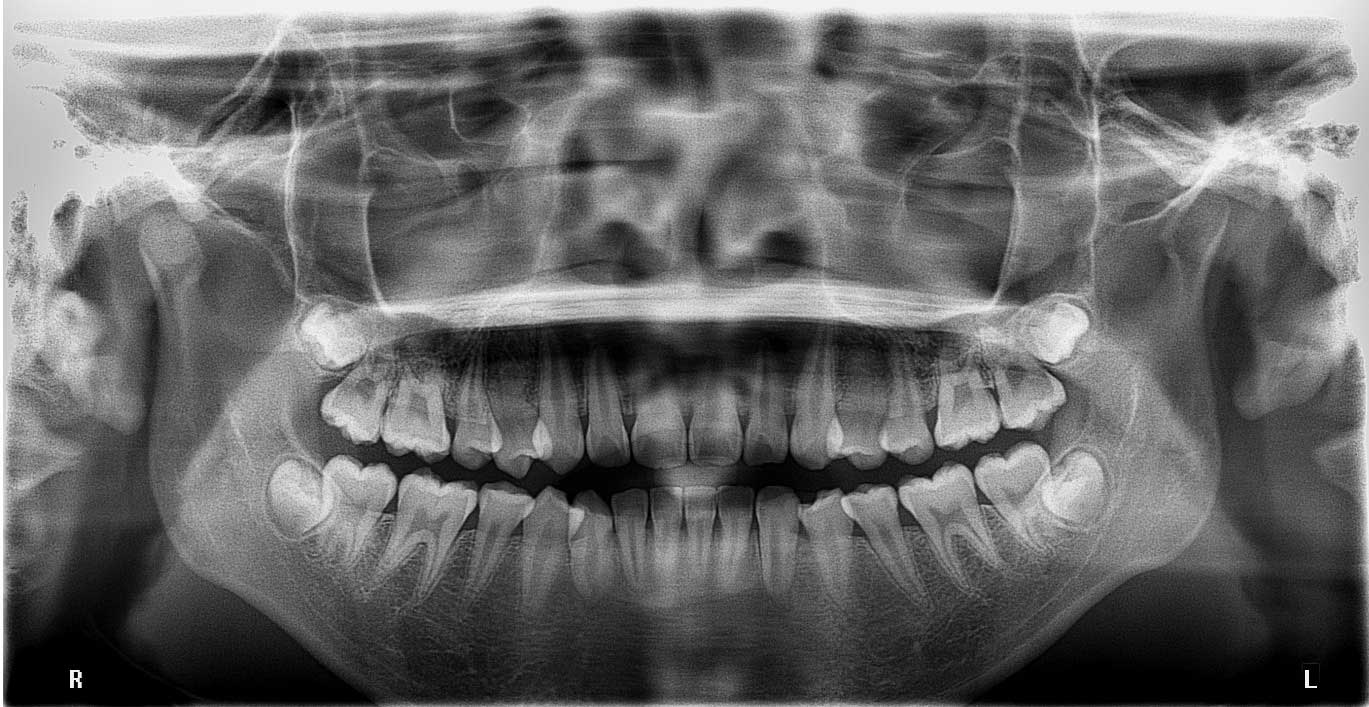

Orthopantomogram (OPG): A jaw-sized x-ray showing all teeth, upper and lower jaw bones, jaw joints, and maxillary sinuses.

OPG Before AI-Guided Detection